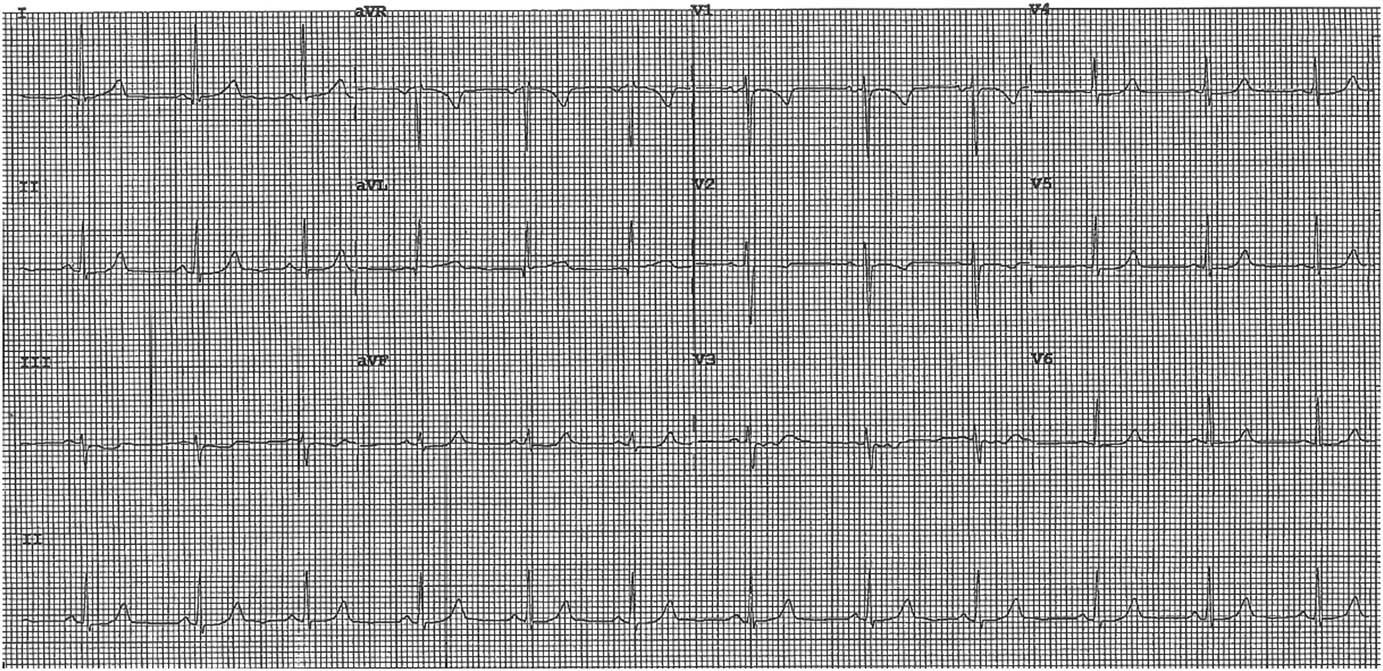

On exam, she was afebrile with a heart rate of 81, a blood pressure of 171/108, and was saturating 100% on room air. On auscultation, there was good air entry bilaterally and normal heart sounds with no murmurs. No pain or edema was found in her lower extremities. Her ECG is shown in Figure 1. Her chest pain and shortness of breath improved after approximately 15 minutes with only mild retrosternal discomfort lasting a further 2 hours.

Figure 1 ECG on Presentation.